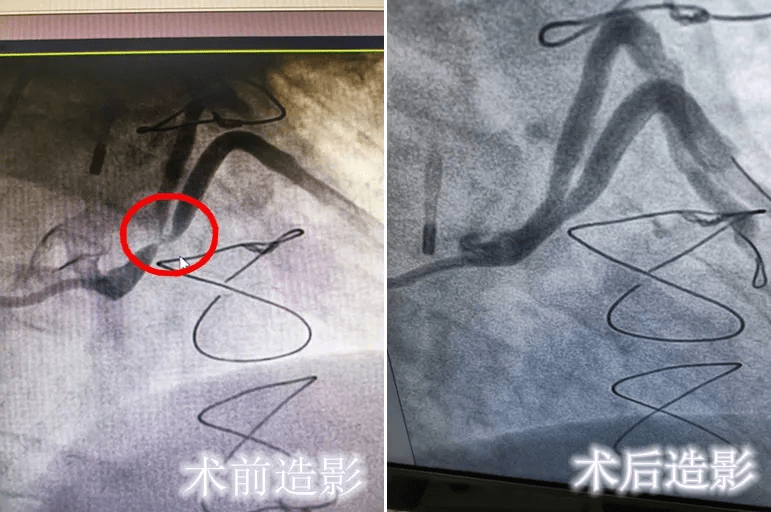

七旬老人心脏搭桥14年后,三支桥血管狭窄程度均超90%!